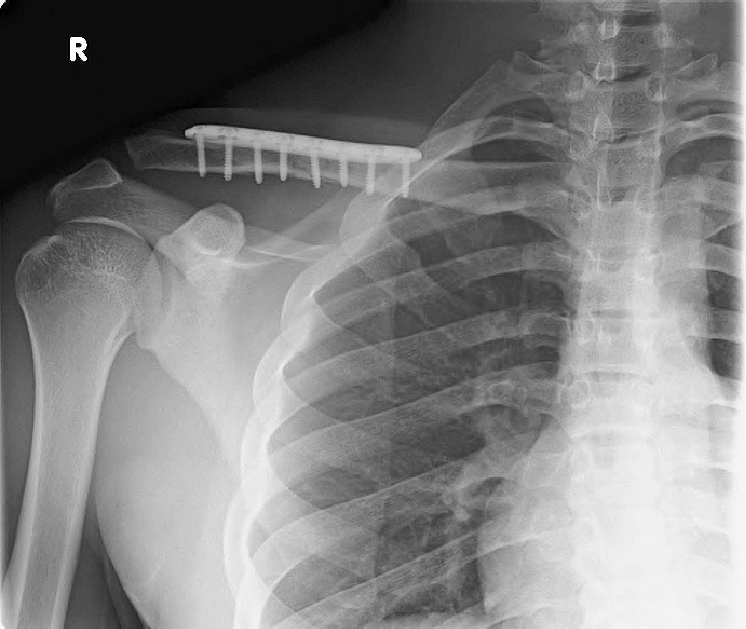

ключицу

Титановая пластина на ключицу 59 фото